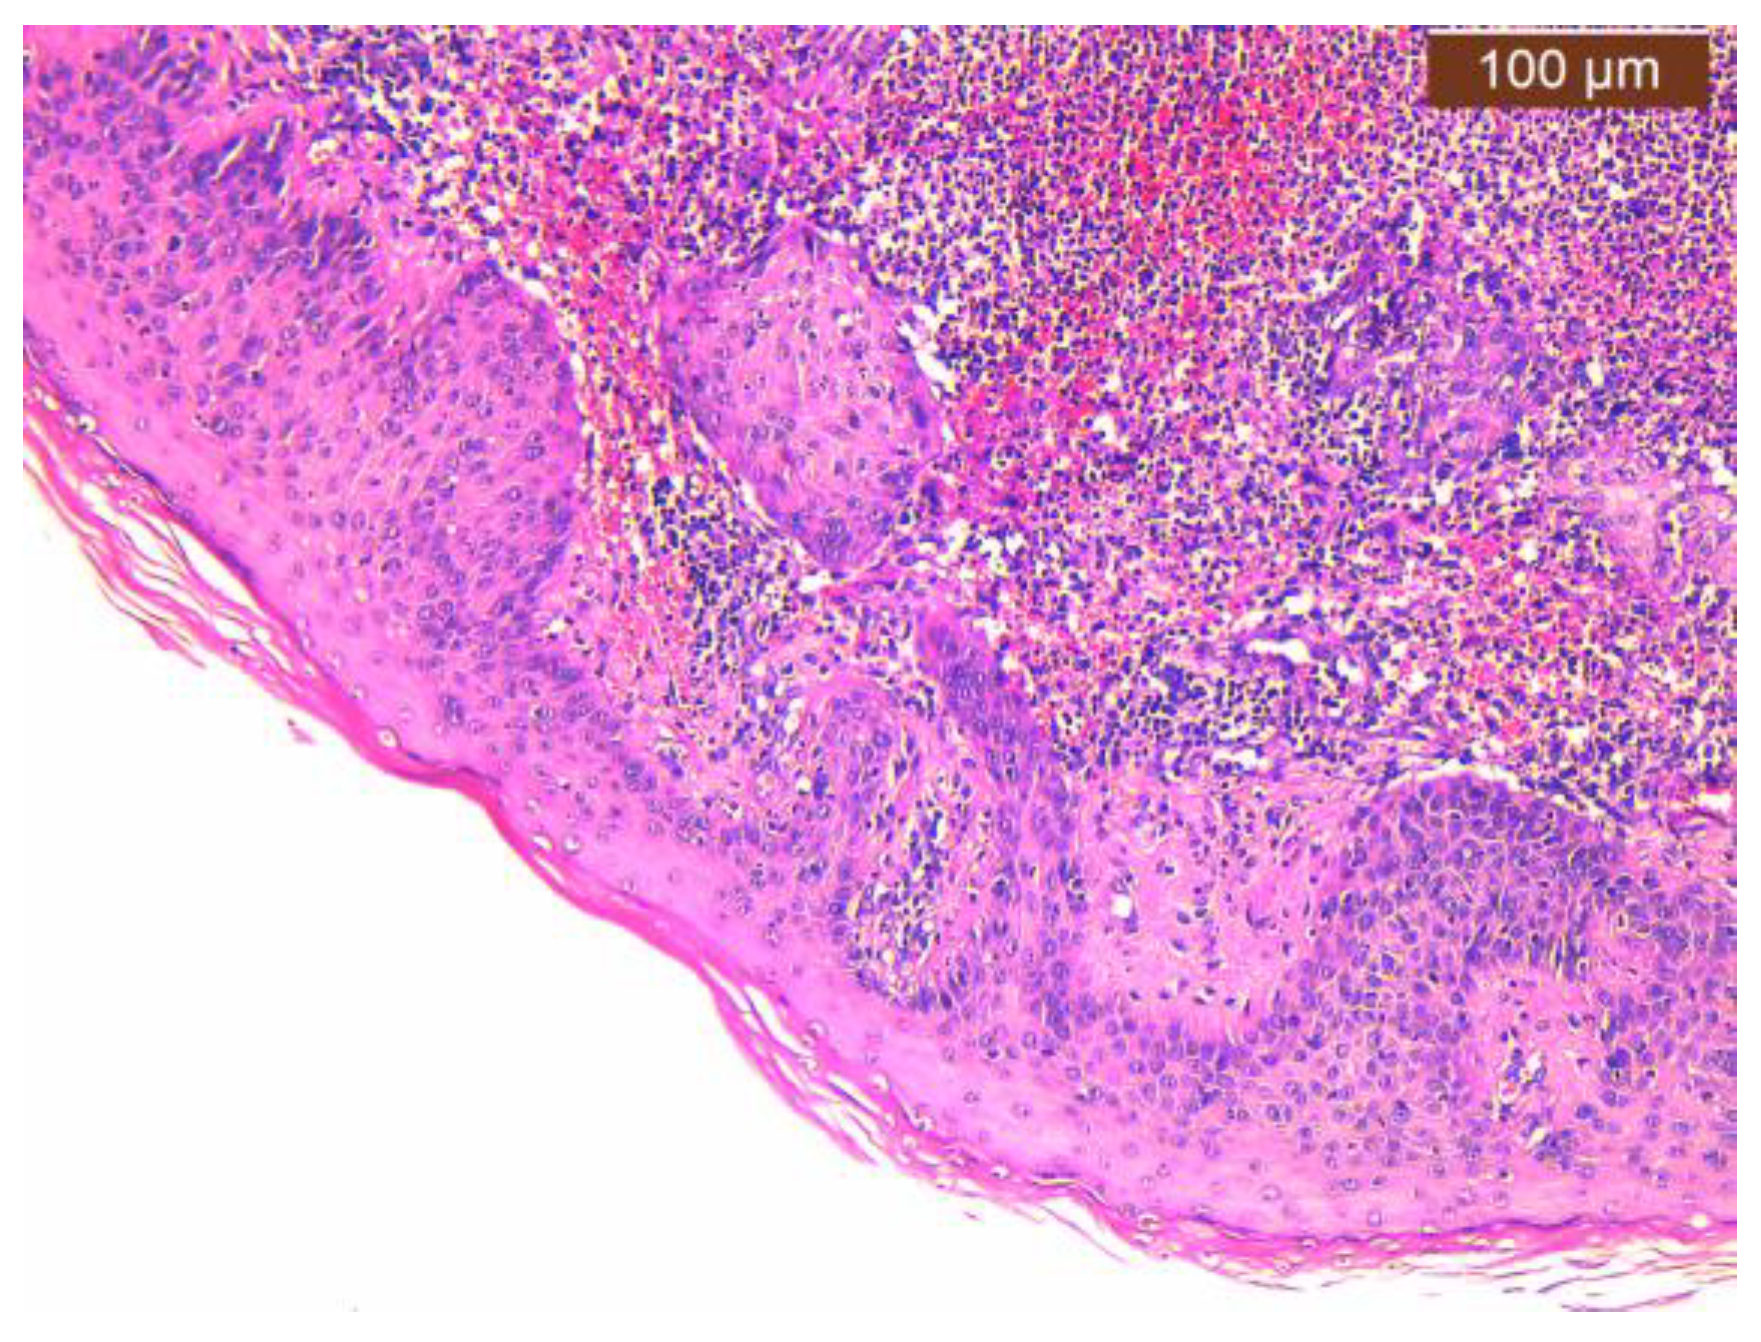

2.2. Histopathology Findings